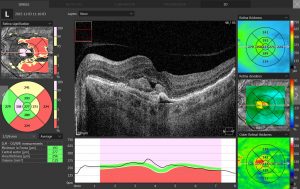

Outre des images OCT précises et un diagnostic du nerf optique, SOCT Copernicus fournit un support analytique aux images générées, y compris des cartes et des graphiques présentant les déformations de l’épaisseur de la rétine et du RNFL et de l’EPR.

| Retina analysis |

Retina thickness, Inner retinal thickness, Outer retinal thickness,

RNFL+GCL+IPL thickness, GCL+IPL thickness, RNFL thickness, RPE deformation, IS/OS thickness |

| Glaucoma analysis |

RNFL, ONH morphology, DDLS, Ganglion analysis as RNFL+GCL+IP

and GCL+IPL, OU and Hemisphere asymmetry |